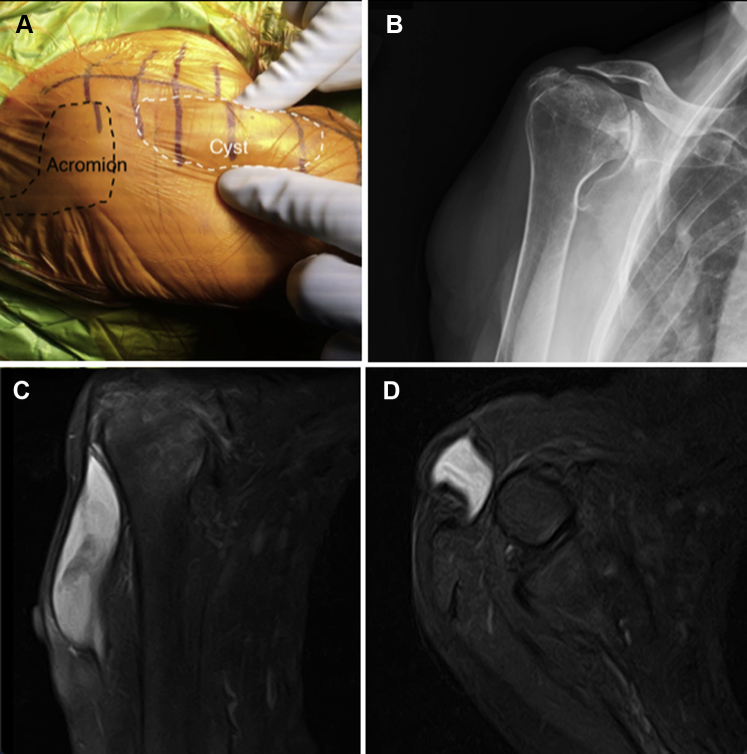

There was a palpable and visible soft-tissue mass on the anterolateral aspect of the shoulder, clinically measuring 7 × 2 × 2 cm (Fig. 1, A). It was soft and mobile, overlying the anterolateral deltoid. There were no overlying skin changes. The patient had normal function in the axillary nerve, including normal sensation in the lateral shoulder and intact function to all 3 heads of the deltoid.

Figure 1.

Trans-deltoid synovial cyst. (A) A photograph of the patient in the semi–beach-chair position shows the outlined acromion (black dashed line) and outlined cyst (white dashed line). The mass was visible and palpable through the middle head of the deltoid. (B) Preoperative Grashey radiograph showing severe cuff tear arthropathy with significant superior erosion, a Sirveaux type E2 deformity, and 27° of superior inclination. (C) Coronal image showing the communication of the subcutaneous fluid-filled cyst with the subacromial space, as well as the craniocaudal extension of the cyst. (D) Axial image at the level of the glenoid showing the trans-deltoid communication of the cyst through the middle head of the deltoid.

The patient’s radiographs revealed end-stage cuff tear arthropathy, with a severe Sirveaux type E2 pattern of superior wear and 27° of inclination, with a small portion of intact glenoid inferiorly (Fig. 1, B). We planned to perform an RSA with autologous humeral head bone grafting to the glenoid, as well as removal of the mass. The patient underwent a computed tomography scan for preoperative planning for the glenoid component and a magnetic resonance imaging (MRI) scan for evaluation of the mass.

The MRI scan revealed a fluid-filled synovial cyst extending from the subacromial space through the middle head of the deltoid, with a 4 × 1–cm defect in the muscle belly (Fig. 1, C and D). The 1-cm deltoid defect was in an anterior-posterior orientation. The cyst appeared to have undergone septation into 2 parts, the first measuring 8 × 3 × 2 cm and the second, immediately adjacent, measuring 2 × 2 × 1 cm. There also appeared to be some early detachment of the adjacent segments of the middle deltoid away from the acromion. We obtained the patient’s consent to perform excision of the cyst and repair of the deltoid. Given the middle deltoid’s importance in RSA, we planned to possibly augment the repair with human dermal allograft if repair to the acromion was necessary. If primary repair was not possible, we planned to perform a deltoid rotationplasty to restore the integrity of the middle head of the deltoid.10